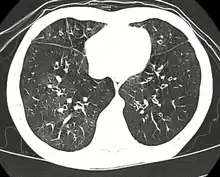

![]() | |

| High resolution CT scan showing bronchiolitis obliterans with mosaic attenuation, bronchiectasis, air trapping and bronchial thickening[3] | |

Medical imaging

Early in the disease chest radiography is typically normal but may show hyperinflation.[6] As the disease progresses a reticular pattern with thickening of airway walls may be present.[4][6] HRCT can also show air trapping when the person being scanned breathes out completely; it can also show thickening in the airway and haziness in the lungs.[11] A common finding on HRCT is patchy areas of decreased lung density, signifying reduced vascular caliber and air trapping. This pattern is often described as a "mosaic pattern", and may indicate bronchiolitis obliterans.[6]